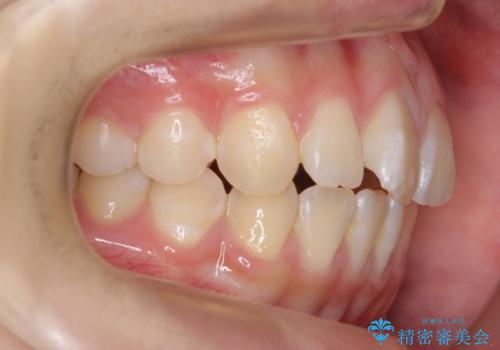

出っ歯 軽度のがたつき インビザラインで

前歯にオープンバイト気味の症状がありましたが、前歯を後ろに下げることでしっかりかませています。

前歯のずれも治り、しっかり下がりました。

前歯を下げるのに、顎間ゴムを使用していただいています。